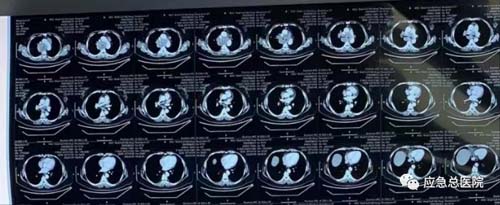

2023年2月,51岁的王女士突发喘憋加重,面色青紫,命悬一线。回到2022年1月,王女士于外院发现右肺肿物伴多发淋巴结肿大,诊断为肺部恶性肿瘤,因无手术机会盲目服靶向药物治疗,但治疗效果甚微,喘憋日益加重,无法入睡。走投无路之际,经人介绍,患者得知应急总医院建立了呼吸道梗阻绿色通道,于是,患者在家人陪同下于2023年2月1日从黑龙江乘火车连夜赶往应急总医院寻求治疗。

王女士来到急诊时,情况十分危急,肺部肿物巨大,气道狭窄段过长,且包绕心脏及主动脉,严重的憋喘导致患者出现了供氧不足、室上性心动过速,心率高达190次/分。呼吸与危重症医学科2部主任张楠教授指示:迅速收治,MDT会诊后紧急手术。高鸿教授迅速为患者办理了住院,并紧急联系心内科、麻醉科等多学科会诊,共同评估患者病情。高鸿教授结合多年临床经验,稳准快制定了救治方案———气管镜下放置气管支架为开放气道夺取一线生机。

术中患者喘憋严重,无法平卧,全麻后于半坐位开始接受治疗。高鸿教授手握硬镜站在凳子上进行手术操作,硬镜刚一插入,患者心率、血压、血氧都出现下降,但随着高鸿教授迅速将硬镜插入近隆突处,心率、血压、血氧迅即出现好转,取病理、放入大Y形金属覆膜支架,仅仅6分钟,患者中央气道狭窄迅速缓解,呼吸顺畅,生命体征恢复正常,在场所有人员都松了一口气。